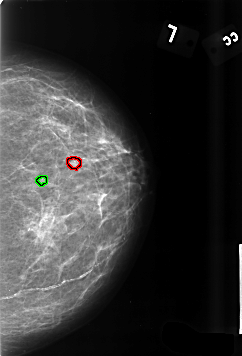

FILE: B_3435_1.LEFT_CC.OVERLAY

TOTAL_ABNORMALITIES 2

ABNORMALITY 1

LESION_TYPE CALCIFICATION TYPE PLEOMORPHIC DISTRIBUTION CLUSTERED

ASSESSMENT 4

SUBTLETY 2

PATHOLOGY BENIGN

TOTAL_OUTLINES 1

BOUNDARY

ABNORMALITY 2